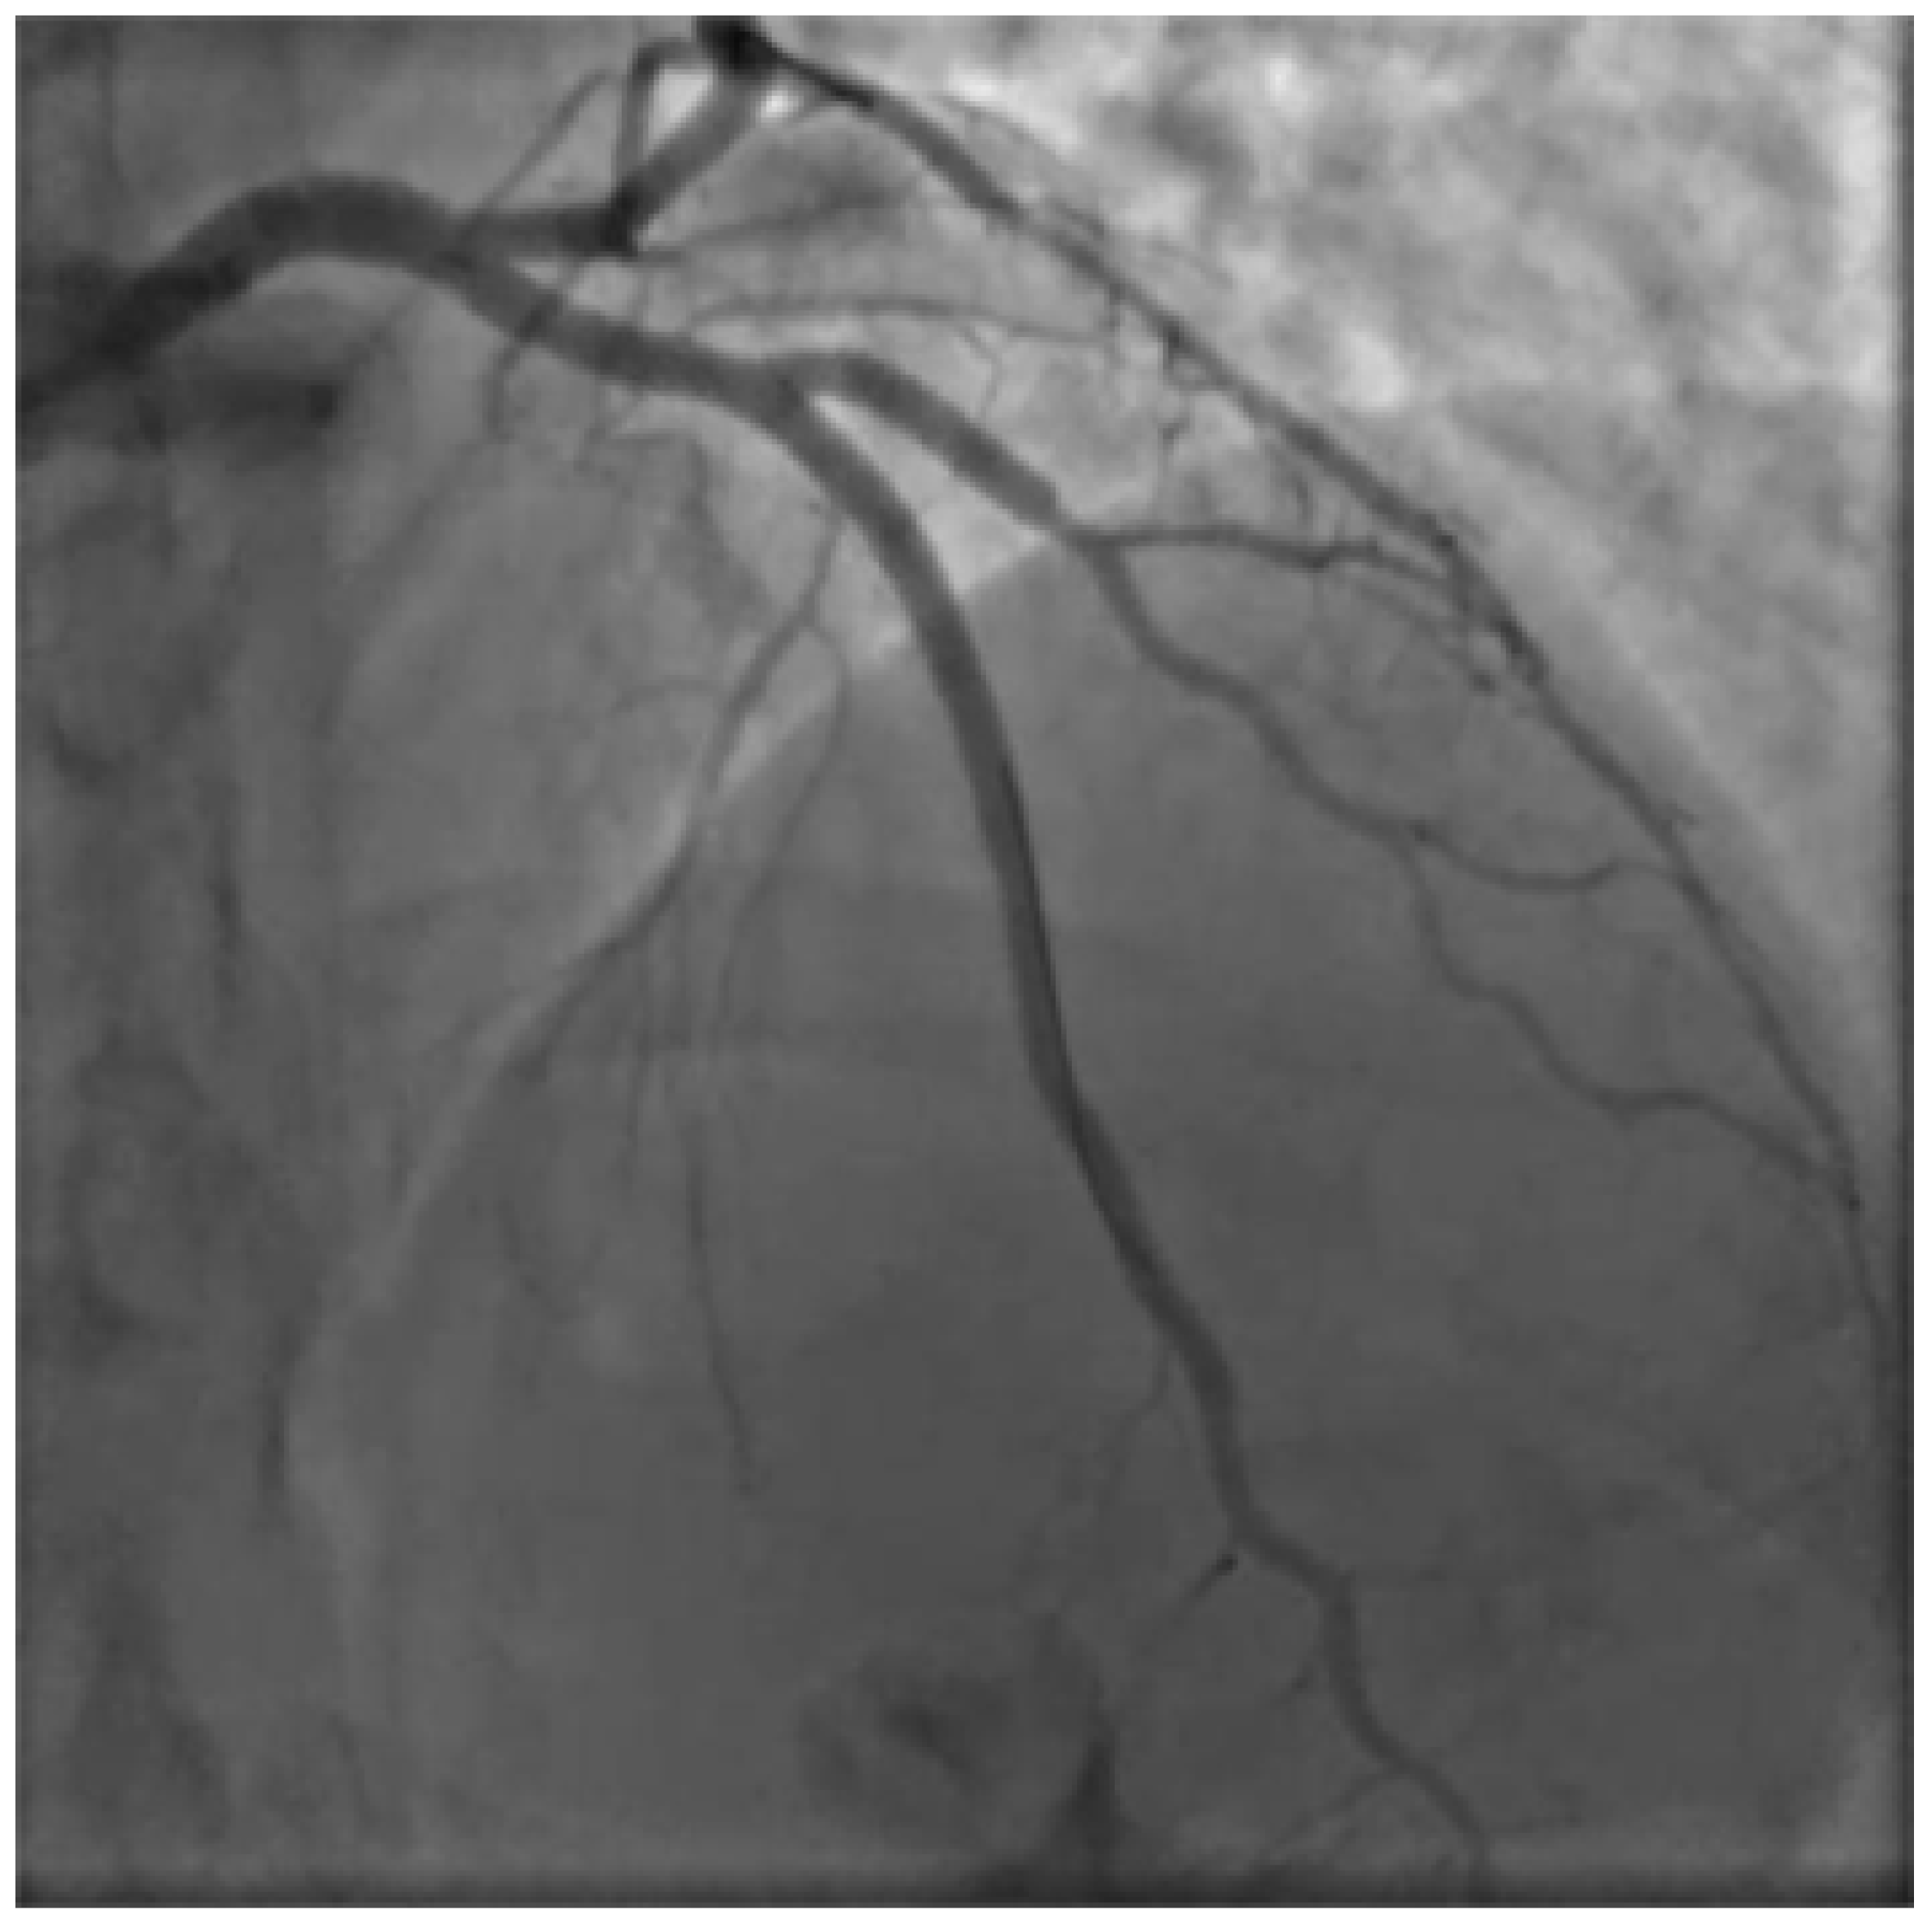

Figure 2. Basal PA caudal projection.

Percutaneous coronary intervention was therefore considered appropriate and a purposely undersized EBU 3.0 6F was selected. Regarding mechanical circulatory support only intra-aortic balloon pump was available. After rapid consultation, considering the insertion of the device, a decision was made to not proceed given the potential lengthening of the procedure, the need for femoral access and the issue of scanning the fetus with the XR detector. A safety wire, Terumo Runthrough floppy, was immediately placed on the patent left circumflex artery whilst after failing wiring on the left anterior descending with a Balance Middleweight wire a Sion wire was advanced up to the apical LAD. An IVUS run confirmed distal true lumen wire position showing a short subintimal track without compromise of any major side branch (Figure 2, Figure 3, Figure 4 and Figure 5).